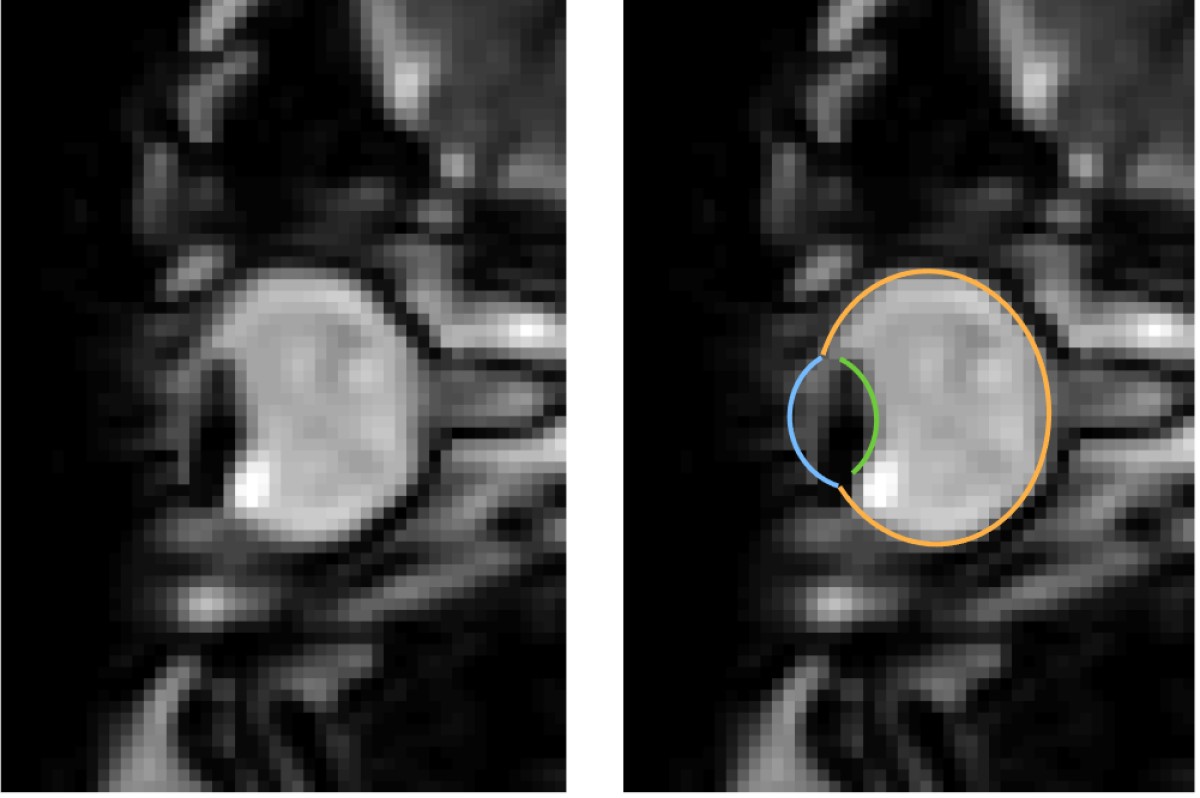

MRT-Aufnahmen von Augenbewegungen beim Blinzeln: Das Auge wird in die Augenhöhle zurückgezogen. Das linke Bild zeigt jeweils nur die dynamischen MRT-Daten, das rechte zusätzlich dazu die Segmentierung des Auges durch den MREyeTrack. Die Fotostecke bestehend aus sechs Bildern stellt die Augenbewegung dar.© WWU - Johannes Kirchner

Augenbewegungen werden typischerweise mit sogenannten Eyetrackern gemessen, also Hochgeschwindigkeitskameras, die die Position der Pupille filmen. Einige Aspekte von Augenbewegungen lassen sich damit jedoch nicht messen. „Es ist uns gelungen, ein Verfahren zu entwickeln, das Augenbewegungen in bisher unerreichter zeitlicher Auflösung mit Echtzeit-MRT-Sequenzen misst. So konnten wir mit unserer Methode zum Beispiel zeigen, dass der komplette Augapfel beim Blinzeln in die Augenhöhle zurückgezogen wird“, erläutert Autor Johannes Kirchner, wissenschaftlicher Mitarbeiter am Institut für Psychologie der WWU. Die Methode haben die WWU-Wissenschaftler mit der Co-Autorin Prof. Dr. Tamara Watson von der Western Sydney University entwickelt.

MRT ist ein relativ langsames Verfahren, die zeitliche Auflösung bewegt sich normalerweise im Bereich von Sekunden oder Minuten. Augenbewegung hingegen sind schnell und dauern typischerweise nur ein paar Dutzend Millisekunden an. Entwicklungen in den vergangenen zehn Jahren haben es jedoch ermöglicht, 2-D-MRT-Aufnahmen mit bis zu 20 Millisekunden zeitlicher Auflösung zu produzieren. Diese ultraschnellen Verfahren kommen vor allem bei der Herzbildgebung zum Einsatz und werden bislang nicht auf die Messung von Augenbewegungen angewandt. „In unseren Aufnahmen haben wir eine zeitliche Auflösung von etwa 35 Millisekunden erzielt. Da bei einer gesamten Messzeit von ein paar Minuten mehr als 10.000 Bilder entstehen, braucht man, um tatsächliches Eyetracking zu betreiben, einen vollautomatischen Algorithmus, um diese Daten auszuwerten“, schildert Mitautor Prof. Dr. Markus Lappe, Leiter des Lehrstuhls für Allgemeine Psychologie und kognitive Neurowissenschaften am Institut für Psychologie der WWU. „Mit ‚MREyeTrack’ haben wir einen solchen sogenannten Segmentierungsalgorithmus entwickelt, der es erstmals ermöglicht, vollautomatisch Position und Orientierung des Auges in jedem einzelnen Bild zu analysieren.“